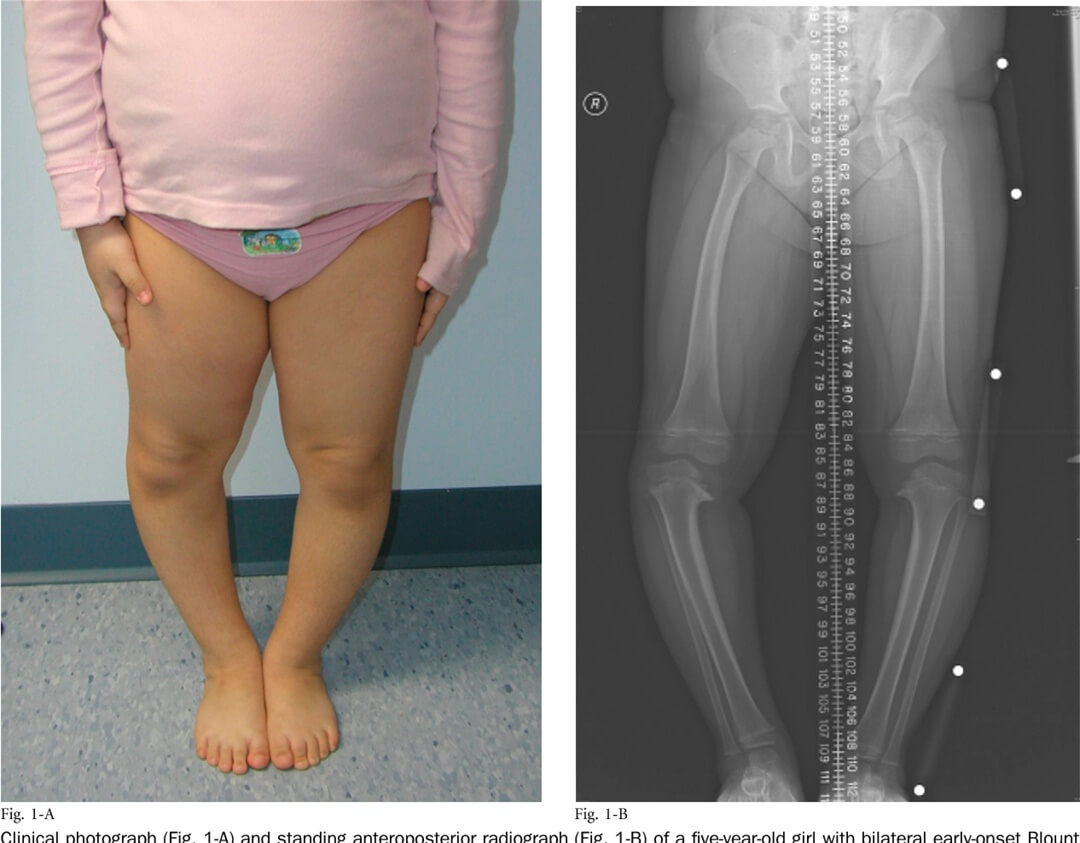

5-летняя девочка с двухсторонней болезнью Блаунта

- Инфантильная форма болезни Блаунта.

Требует пристального внимания. При тяжёлых формах необходимо хирургическое лечение, желательно до 4 лет. При лёгких формах может произойти самостоятельно разрешение заболевания, хотя некоторая литература рекомендует для достижения этого применять антиварусные брейсы (ортезы по типу KAFO – Knee-Ankle-Foot Orthosis). Считается, что данный вариант лечения может применяться у детей не старше 3 лет. При отсутствии эффекта в течении года нужно хирургическое вмешательство.